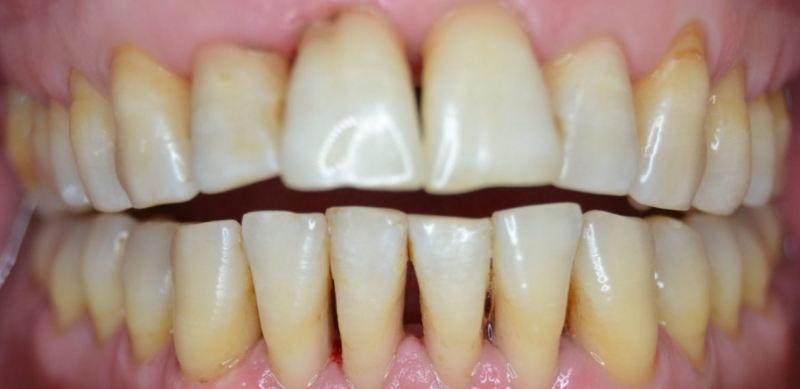

На странице представлено портфолио стоматологий Санкт-Петербурга с работами до и после профессиональной чистки зубов. В нашем портфолио собраны разные клинические случаи: от удаления незначительного налета до снятия массивного поддесневого камня. Здесь вы можете увидеть, как возвращается естественный цвет и внешний вид зубов после процедуры. Изучите результаты до и после чистки зубов, чтобы увидеть реальный эффект и выбрать клинику в Санкт-Петербурге, где профессиональная гигиена поможет вернуть зубам здоровый вид.